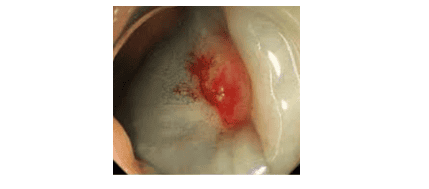

6. Đánh giá polyp bằng phương pháp “tiêm nâng” – dấu hiệu “None-Lifting sign”

Trong kĩ thuật cắt niêm mạc qua nội soi (EMR – Endoscopic Mucosal Resection), được sử dụng để cắt các polyp không cuống, một lượng dung dịch được tiêm vào lớp dưới niêm để nâng tổn thương ở lớp niêm mạc ra khỏi lớp dưới niêm, điều này giúp tránh biến chứng thủng ống tiêu hóa trong thủ thuật.

Tuy nhiên, nếu đã tiêm một lượng dung dịch, nhưng không nâng được tổn thương lên, thì rất có thể tổn thương polyp đã xâm lấn hoặc xơ hoá xuống lớp dưới niêm. Những trường hợp như vậy, hãy cẩn thận, vì có thể đây là polyp ung thư hoá.

Trên đây là một số kĩ thuật được sử dụng tại Hệ thống Bệnh viện Vinmec, được dùng để chẩn đoán khả năng ác tính của polyp trước khi cắt polyp. Đối với các polyp nghi ngờ ác tính, thay vì tiến hành cắt polyp, bác sĩ nội soi sẽ sinh thiết vùng nghi ngờ ác tính trên bề mặt polyp để có hướng xử trí tiếp theo.